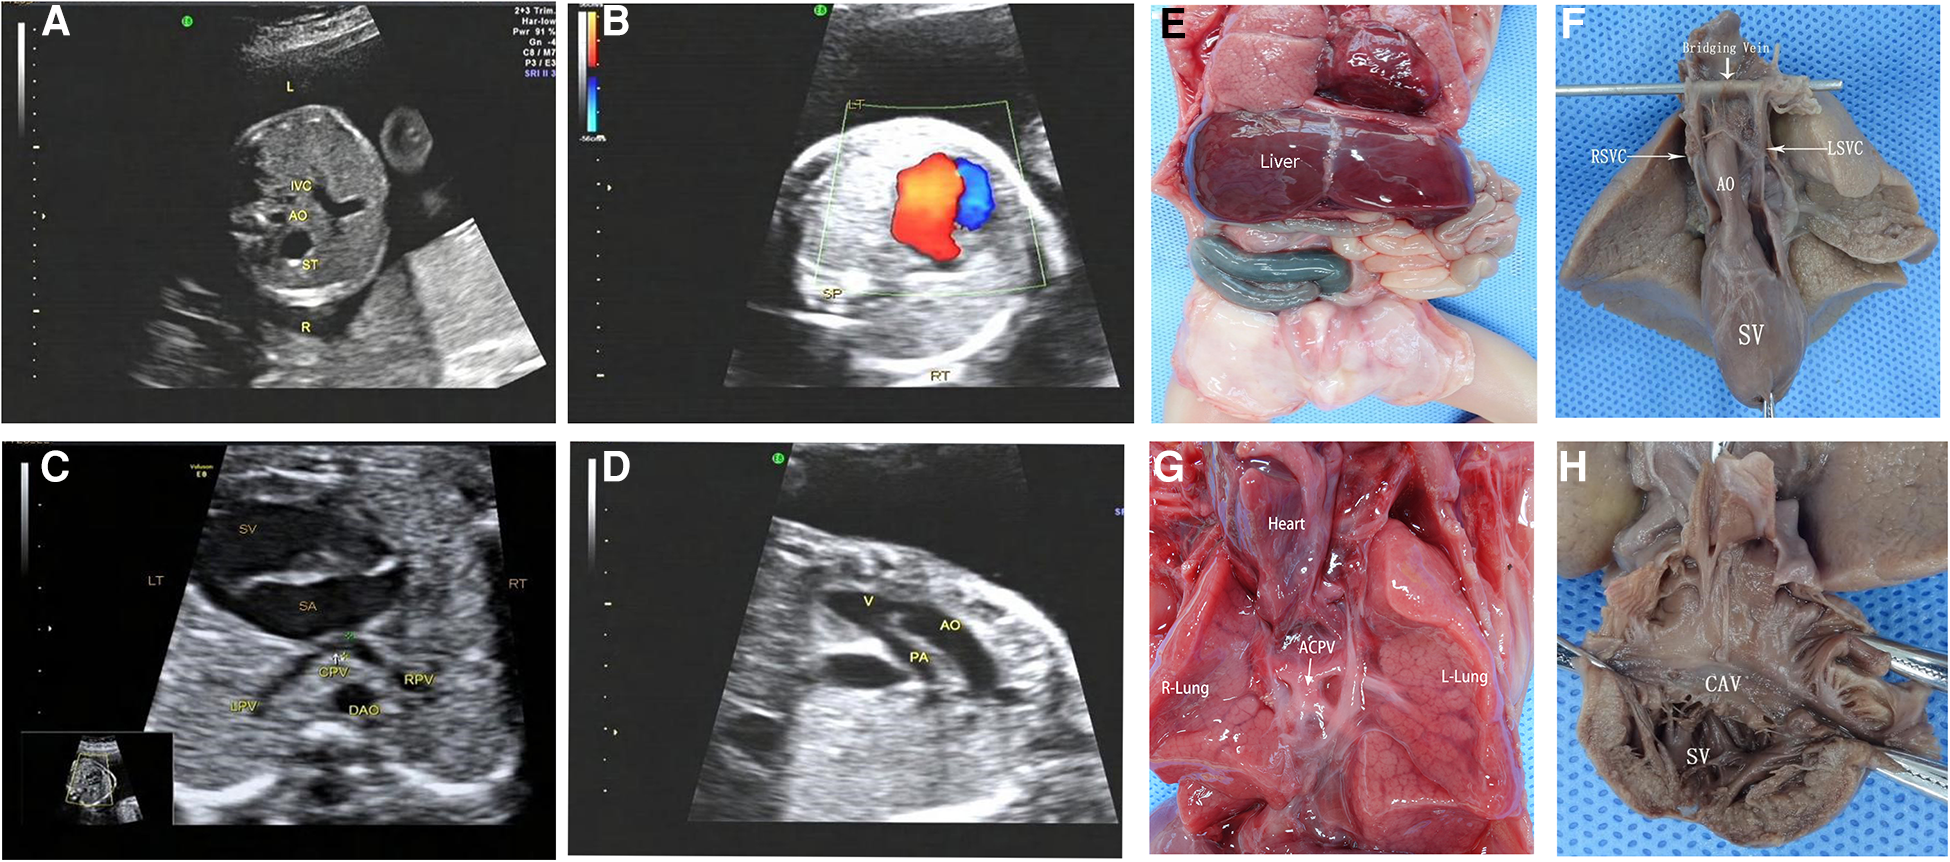

Figure 5

Prenatal ultrasonography and anatomical images of RI fetuses with atresia of common pulmonary vein (ACPV). (A) The AO and IVC were on the left side of the spine, and the IVC was in the left front of the abdominal aorta. (B) One group of common atrioventricular valve blood flow was seen in the CDFI four-chamber section during the diastolic period. (C) Pulmonary veins form a common cavity of the pulmonary vein behind the atrium. (D) The aorta and pulmonary artery originated parallelly from the single ventricle, complicated with pulmonary stenosis. Figure (E–H) anatomical images. (E) Midline liver, intestinal malrotation, the appendix in the right upper abdomen. (F) Single ventricle, double superior vena cava with bridging vein connection. (G) The heart turned upside down, and the pulmonary veins formed a closed common cavity behind the atrium. (H) The heart specimen was clam-opened, exposing a single ventricle consisting mainly of a right ventricle common atrioventricular inlet, and atrioventricular valve. SA, single atrium; SV, single ventricle; LPV, left pulmonary vein; RPV, right pulmonary vein; CPV, common cavity of the pulmonary vein.

One case of the single ventricle was misdiagnosed as an unbalanced atrioventricular septal defect and one case of pulmonary atresia as pulmonary arterial stenosis. In four cases, the spleen was seen in the right posterior part of the stomach, which was misdiagnosed by prenatal ultrasonography. Three cases of APVC were misdiagnosed by ultrasonography, including one case of common vena cava atresia mistaken as complete APVC and two cases as mixed APVC (Figure 5); four APVC cases were overlooked, including one case of abnormal drainage of sub-cardiac pulmonary vein and three cases of common cava atresia of a pulmonary vein; four cases of the hepatic vein were missed by ultrasound scanning.

Atresia of the common pulmonary vein (ACPV) is a rare congenital cardiovascular malformation. The left and right pulmonary veins form a common pulmonary vena cava, which is not connected to the left atrium, right atrium, or other main body veins (29). As ACPV is often located in the dorsal side of the heart, it is prone to missed diagnosis or misdiagnosis as a complete anomalous pulmonary venous connection (30). However, vascular casting greatly assists ultrasonologists in examining intracardiac malformations and systemic and pulmonary venous connections, broadening their understanding of the disease (31). The postnatal mortality rate of ACPV is extremely high, and the afflicted rarely survive for more than 4 weeks (32). The possibility of ACPV should be considered when prenatal ultrasound detects a common pulmonary venous lumen behind the fetal atrium but fails to clearly show the vertical venous drainage of the common pulmonary venous lumen. In such a scenario, the gain of blood flow should be adequately adjusted to prevent excessive gain from being mistaken for the running drainage vessel.